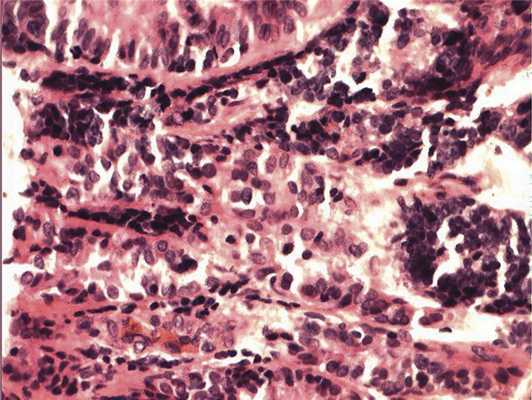

Отмечалось наличие ленточных структур из низкодифференцированных эпителиальных клеток (рис. 4). Параллельно встречались участки солидного строения из клеток с гиперхромными ядрами с признаками клеточного и ядерного полиморфизма. В них почти исчезает строма, появляются митозы, встречаются участки дистрофии и некроза (рис. 5). Опухоль врастает в ткань ДЗН с переходом за laminacribrosa, но не достигает линии отсечения (рис. 6). В таком виде опухоль обладает местнодеструирующим характером роста и может давать метастазы, глубоко инфильтрируя прилежащую к ДЗН ткань хориоидеи. Окончательный гистологический диагноз: злокачественная медуллоэпителиома центрального отдела сетчатки с вовлечением ДЗН и инвазией перипапиллярной хориоидеи, с глубоким прорастанием по зрительному нерву, не достигая линии отсечения.

Рис. 4. Формирование полос из низкодифференцированных нейроэпителиальных клеток. Окраска гематоксилином и эозином. Ув. 400.